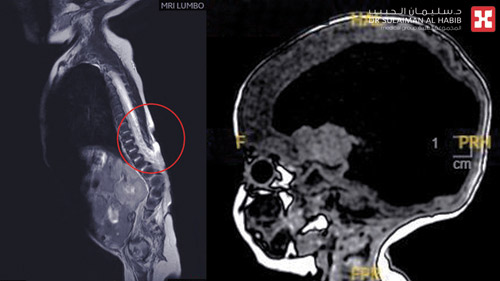

ذكر ذلك الدكتور بهاء الدين محسن، استشاري جراحة المخ والأعصاب والعمود الفقري رئيس الفريق الطبي المعالج. والذي قال إن الفحص الذي أجرى للطفل فور وصوله للمستشفى أظهر وجود فتحة وشرخ كبير بطول (7) سم أسفل الظهر، وتم على الفور إخضاعه لمزيد من الفحوصات الدقيقة حيث كشفت النتائج أن الرضيع وُلد بتشوه خلقي نادر يُعرف باسم «القيلة النخاعية السحائية»، وهو نوع من السنسنة المشقوقة التي تُصيب العمود الفقري، حيث يظهر الحبل الشوكي وغطاؤه (السحايا)، من خلال فتحة بالعمود الفقري، وقد تؤدي إلى درجات متفاوتة من الشلل ومشاكل بالأمعاء والمثانة، ومضاعفات أخرى تعتمد على شدة الخلل وموقعه، كما أظهرت النتائج وجود تقوس بالعمود الفقري تحت مكان التشوه الخلقي.

وأضاف الدكتور بهاء بأن صعوبة معالجة هذه الحالة تكمن في تأخر وصوله للمستشفى، وإصابته بالتهاب في فتحة الظهر والدماغ، بالإضافة إلى حدوث التهابات بالسحايا والاستسقاء الدماغي وكذلك متلازمة الكياري، وبناءاً على النتائج تم تحويل الرضيع إلى العناية المركزة للأطفال (N.I.C.U)، وإعطائه الأدوية التحفظية والمضادات الحيوية الوريدية، وعقب انتهاء الفريق الطبي من دراسة كافة نتائج الفحوصات، تم وضع خطة علاجية تقتضي التدخل الجراحي لعلاج التشوه الخلقي على عدة مراحل. حيث تم عمل إغلاق جزئي للقيلة النخاعية وتركيب أنبوب لتصريف السائل الشوكي، ومعالجة الالتهاب السحائي أسفل الظهر، تبع ذلك إخضاع الطفل لعملية دقيقة استغرقت ساعتين تحت التخدير العام، وتم فيها تصحيح مسار الأعصاب وتغليف عظام العمود الفقري والنخاع، وإغلاق فتحة الظهر بالإستعانة باستشاريي جراحة التجميل والترميم، الذين بذلوا جهداً كبيراً لتغطية التشوه، من خلال عمل شرائح نسيجية لإغلاق الفتحة المكشوفة بالظهر، وقد واجه الفريق الطبي صعوبة شديدة في إغلاق الفتحة نتيجة تقوس العمود الفقري.